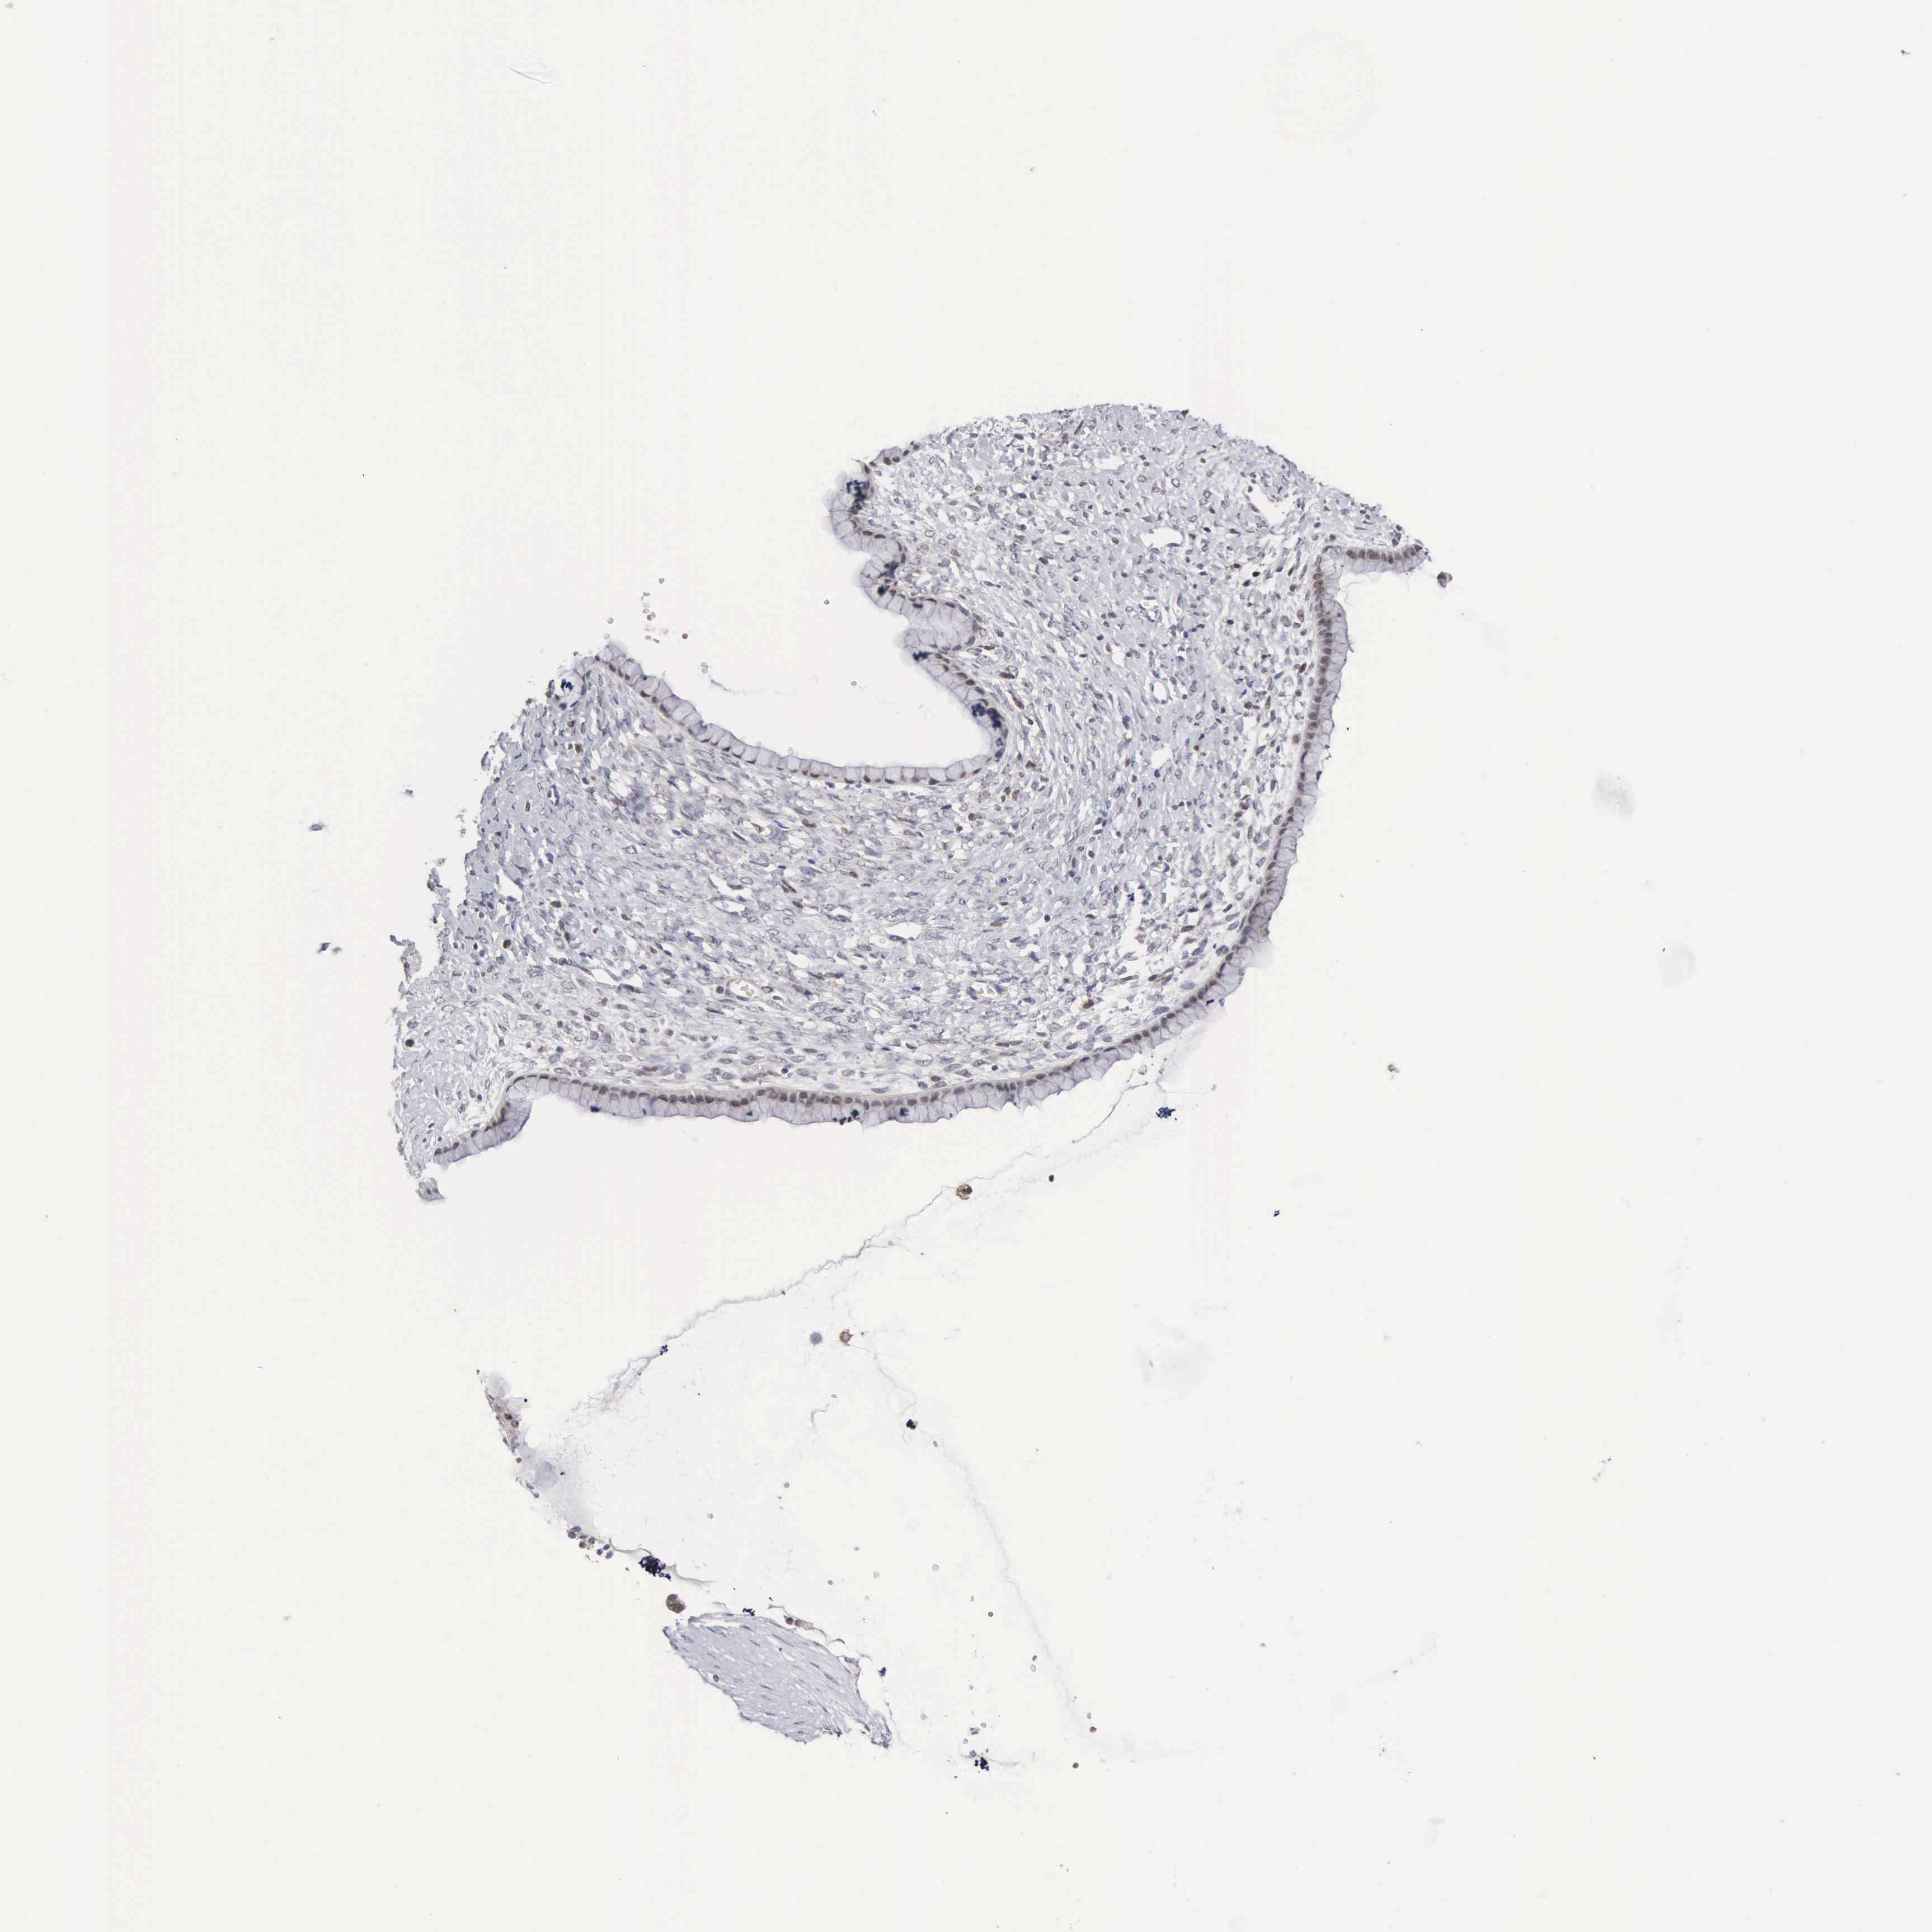

OVARIAN CANCER - Protein expressioni

A mouse-over function shows sample information and annotation data. Click on an image to view it in a full screen mode. Samples can be filtered based on level of antibody staining by selecting one or several of the following categories: high, medium, low and not detected. The assay and annotation is described here.

Note that samples used for immunohistochemistry by the Human Protein Atlas do not correspond to samples in the TCGA dataset.

Antibody stainingi

Antibody staining in the annotated cell types in the current human tissue is reported as not detected, low, medium, or high, based on conventional immunohistochemistry profiling in selected tissues. This score is based on the combination of the staining intensity and fraction of stained cells.

Each image is clickable and will lead to virtual microscopy that enables deeper exploration of all samples and also displays staining intensity scores, fraction scores and subcellular localization as well as patient and tissue information for each sample.

Antibody HPA000779

Staining

High

Medium

Low

Not detected

Intensity

Strong

Moderate

Weak

Negative

Quantity

>75%

75%-25%

<25%

None

Location

Nuclear

Cytoplasmic/membranous

Cytoplasmic/membranous,nuclear

Cystadenocarcinoma, mucinous, NOS

Carcinoma, endometroid

Cystadenocarcinoma, serous, NOS